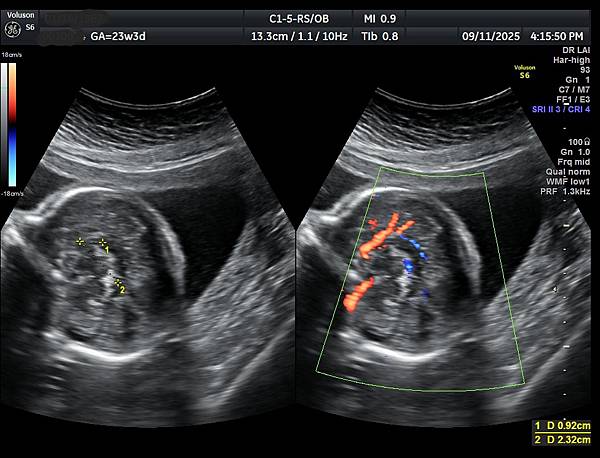

2026年1月9日一位34歲第三胎懷孕21週又6天的孕婦在孕兒診所接受胎兒心臟及高層次超音波檢查,檢查後除了邊緣型前置胎盤、羊水指數正常偏少( AFI: 8.19 cm )之外,沒有異常發現。

孕婦告訴我們第二胎(2024年10月)也是在孕兒診所檢查,因為胎兒心臟檢查出胎兒有血管環(附圖1,動脈導管在氣管右側,主動脈弓在氣管左側,參考第446篇文章),建議抽羊水做晶片檢查,結果胎兒是狄喬治症候群( 附圖 2. ),當年她已抽24000元的NIPS( 附圖 3.)沒有異常發現(包含狄喬治症候群),這一胎她直接抽羊水,還好檢查結果正常。